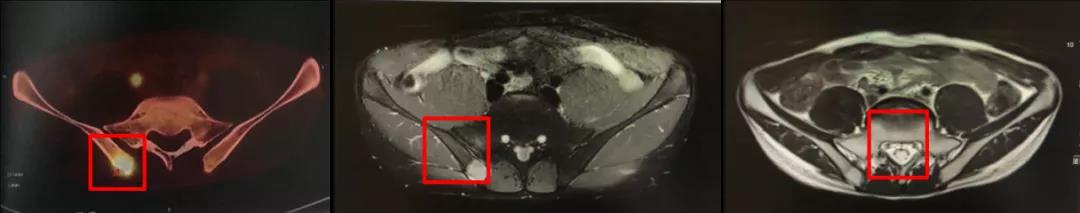

影像学评价:鼻咽MR(2020年7月7日),治疗前后MR变化见图2,可见鼻咽顶后壁黏膜增厚,范围约5mm×5mm;右侧颈部II-V区多发转移淋巴结,大者直径约5mm,病灶较前进一步缩小。右髂骨转移瘤,直径约20mm,范围较前变化不大,强化较前减低。如图2-1(鼻咽部病灶)、2-2(右侧颈部淋巴结病灶)、2-3(右侧髂骨病灶)从左至右分别为治疗前(2020年2月17日)、4程治疗后(2020年3月24日)、放疗后1个月(2020年7月7日)。